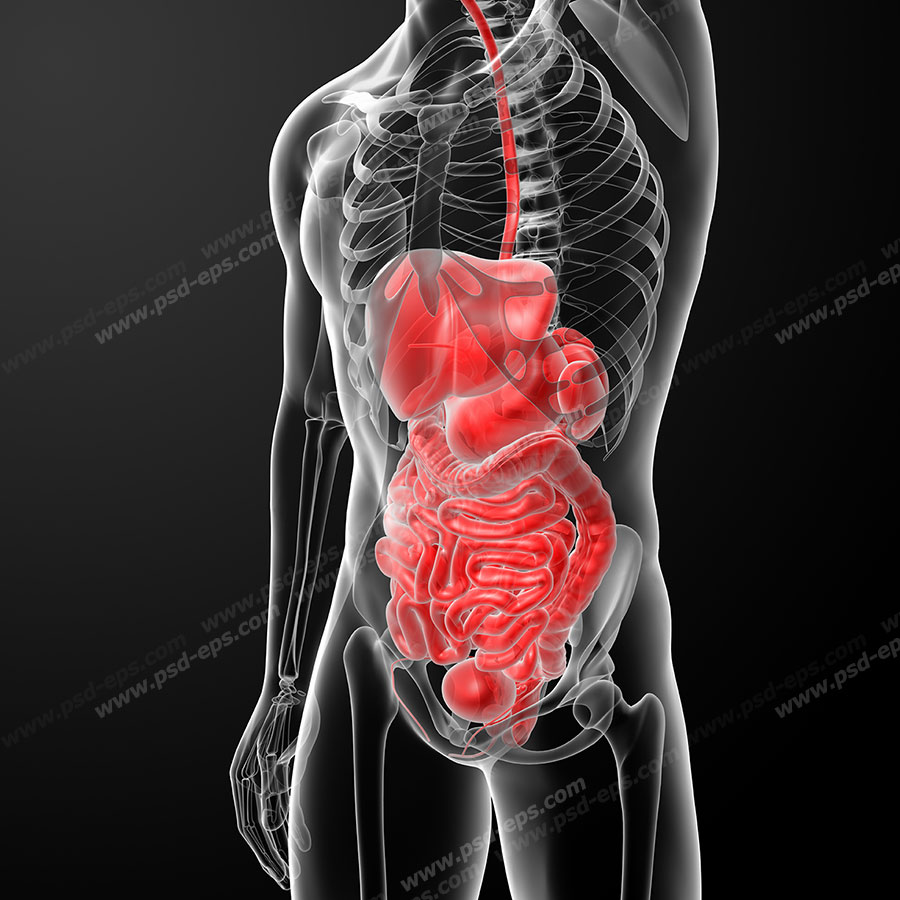

عکس داخل شکم انسان. در این همان طور که مشخص است شکم حالت بیضی شکل پیداکرده و این بیضی که کناره های شکم کشیده شده است. تعداد سلول های بدن انسان حدود ۳۷ ۲ تریلیون تخمین زده شده اند. Abdomen که در زبان عامه به غلط به آن دل نیز می گویند در آناتومی به قسمتی از تنه گفته می شود که مابین دیافراگم از بالا و سطح فوقانی لگن خاصره از پایین قرار دارد. ربات دیدنی ربات انساننمای چینی به صورت یک دختر جوان ساخته شده و جیا جیا نامگذاری شده است این ربات طوری برنامهریزی شده که میتواند صحبت کند و احساسات خود را از طریق تغییرات در چهره حالات.

شکل دوم شکم مادری را نشان می دهد که جنین دختر دارد. وحشت مادر از عکس سونوگرافی جنین داخل شکمش عکس. تصاویر جالب از داخل مغز و نخاع انسان آخرین نیوز. بدن انسان کل ساختار انسان است که سر گردن تنه سینه و شکم دو بازو و دست ها و دو ساق پا و پاها را شامل می شود.